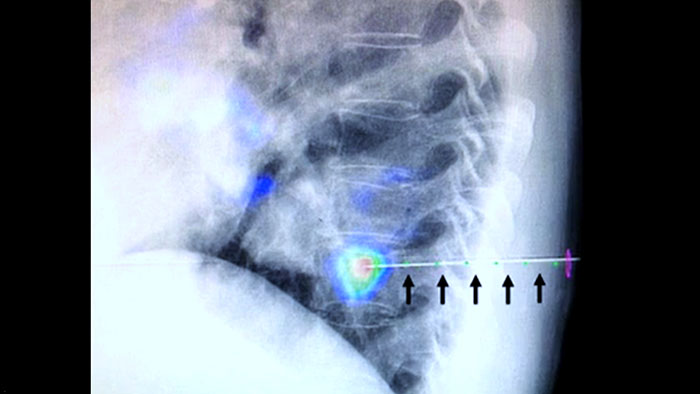

XperGuide bietet eine besonders präzise Live-Bildführung für jede Nadel zur Zielposition. Hierfür wird das Durchleuchtungsbild mit den vorab geplanten Bewegungsverläufen überlagert.3

XperGuide Ablation* bietet umfassende Unterstützung bei der Behandlungsplanung und Echtzeit-Nadelnavigation. Die spezielle Parallaxenkorrektur ermöglicht die Planung von Nadelverläufen bei außermittigen Läsionen.1 Um eine möglichst gute Nadelposition für eine wirksame Ablation zu erreichen, zeigt dieses Tool den virtuellen Nadelverlauf an. Auch die Planung mehrerer Ablationsnadeln wird dadurch unterstützt. Außerdem werden Nadeleigenschaften wie Ablationszone/Isotherm angezeigt, damit die vollständige Tumorabdeckung vor der Ablation verifiziert werden kann.